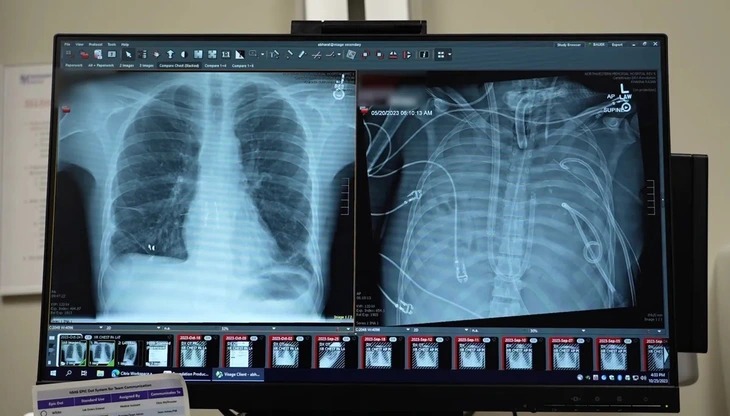

Các bác sĩ Đại học Northwestern tiến hành cắt bỏ phổi hoại tử và gắn phổi nhân tạo, trước khi ghép phổi hiến tặng vào hai ngày sau đó - Ảnh: NORTHWESTERN UNIVERSITY |

Bệnh nhân khỏe mạnh bên lá phổi mới được ghép (trái) và lúc đã cắt bỏ phổi hoại tử - Ảnh: NORTHWESTERN UNIVERSITY |